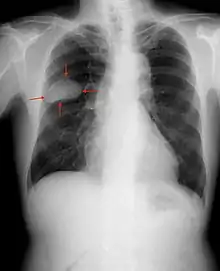

Small-cell carcinoma is most often more rapidly and widely metastatic than non-small-cell lung carcinoma[23] (and hence staged differently). There is usually early involvement of the hilar and mediastinal lymph nodes. [22] The mechanisms of its metastatic progression are not well-understood.[24]